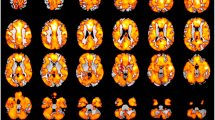

We found that patients with schizophrenia had decreased GMV in the left parietal postcentral region extending to the left frontal regions, right middle temporal gyrus, occipital region and right cerebellum posterior pyramis (Fig. 1 and Table 2).

Relative to healthy comparison subjects, patients with drug-naïve, first-episode schizophrenia showed significantly reduced gray matter volume. (A) Right cerebellum posterior pyramis; (B) Right middle temporal gyrus; (C) Right middle occipital gyrus; (D) Right occipital cuneus gyrus; (E) Left parietal postcentral gyrus; (F). Right frontal precentral gyrus (G) Left frontal precentral gyrus; (H) Left superior frontal gyrus.